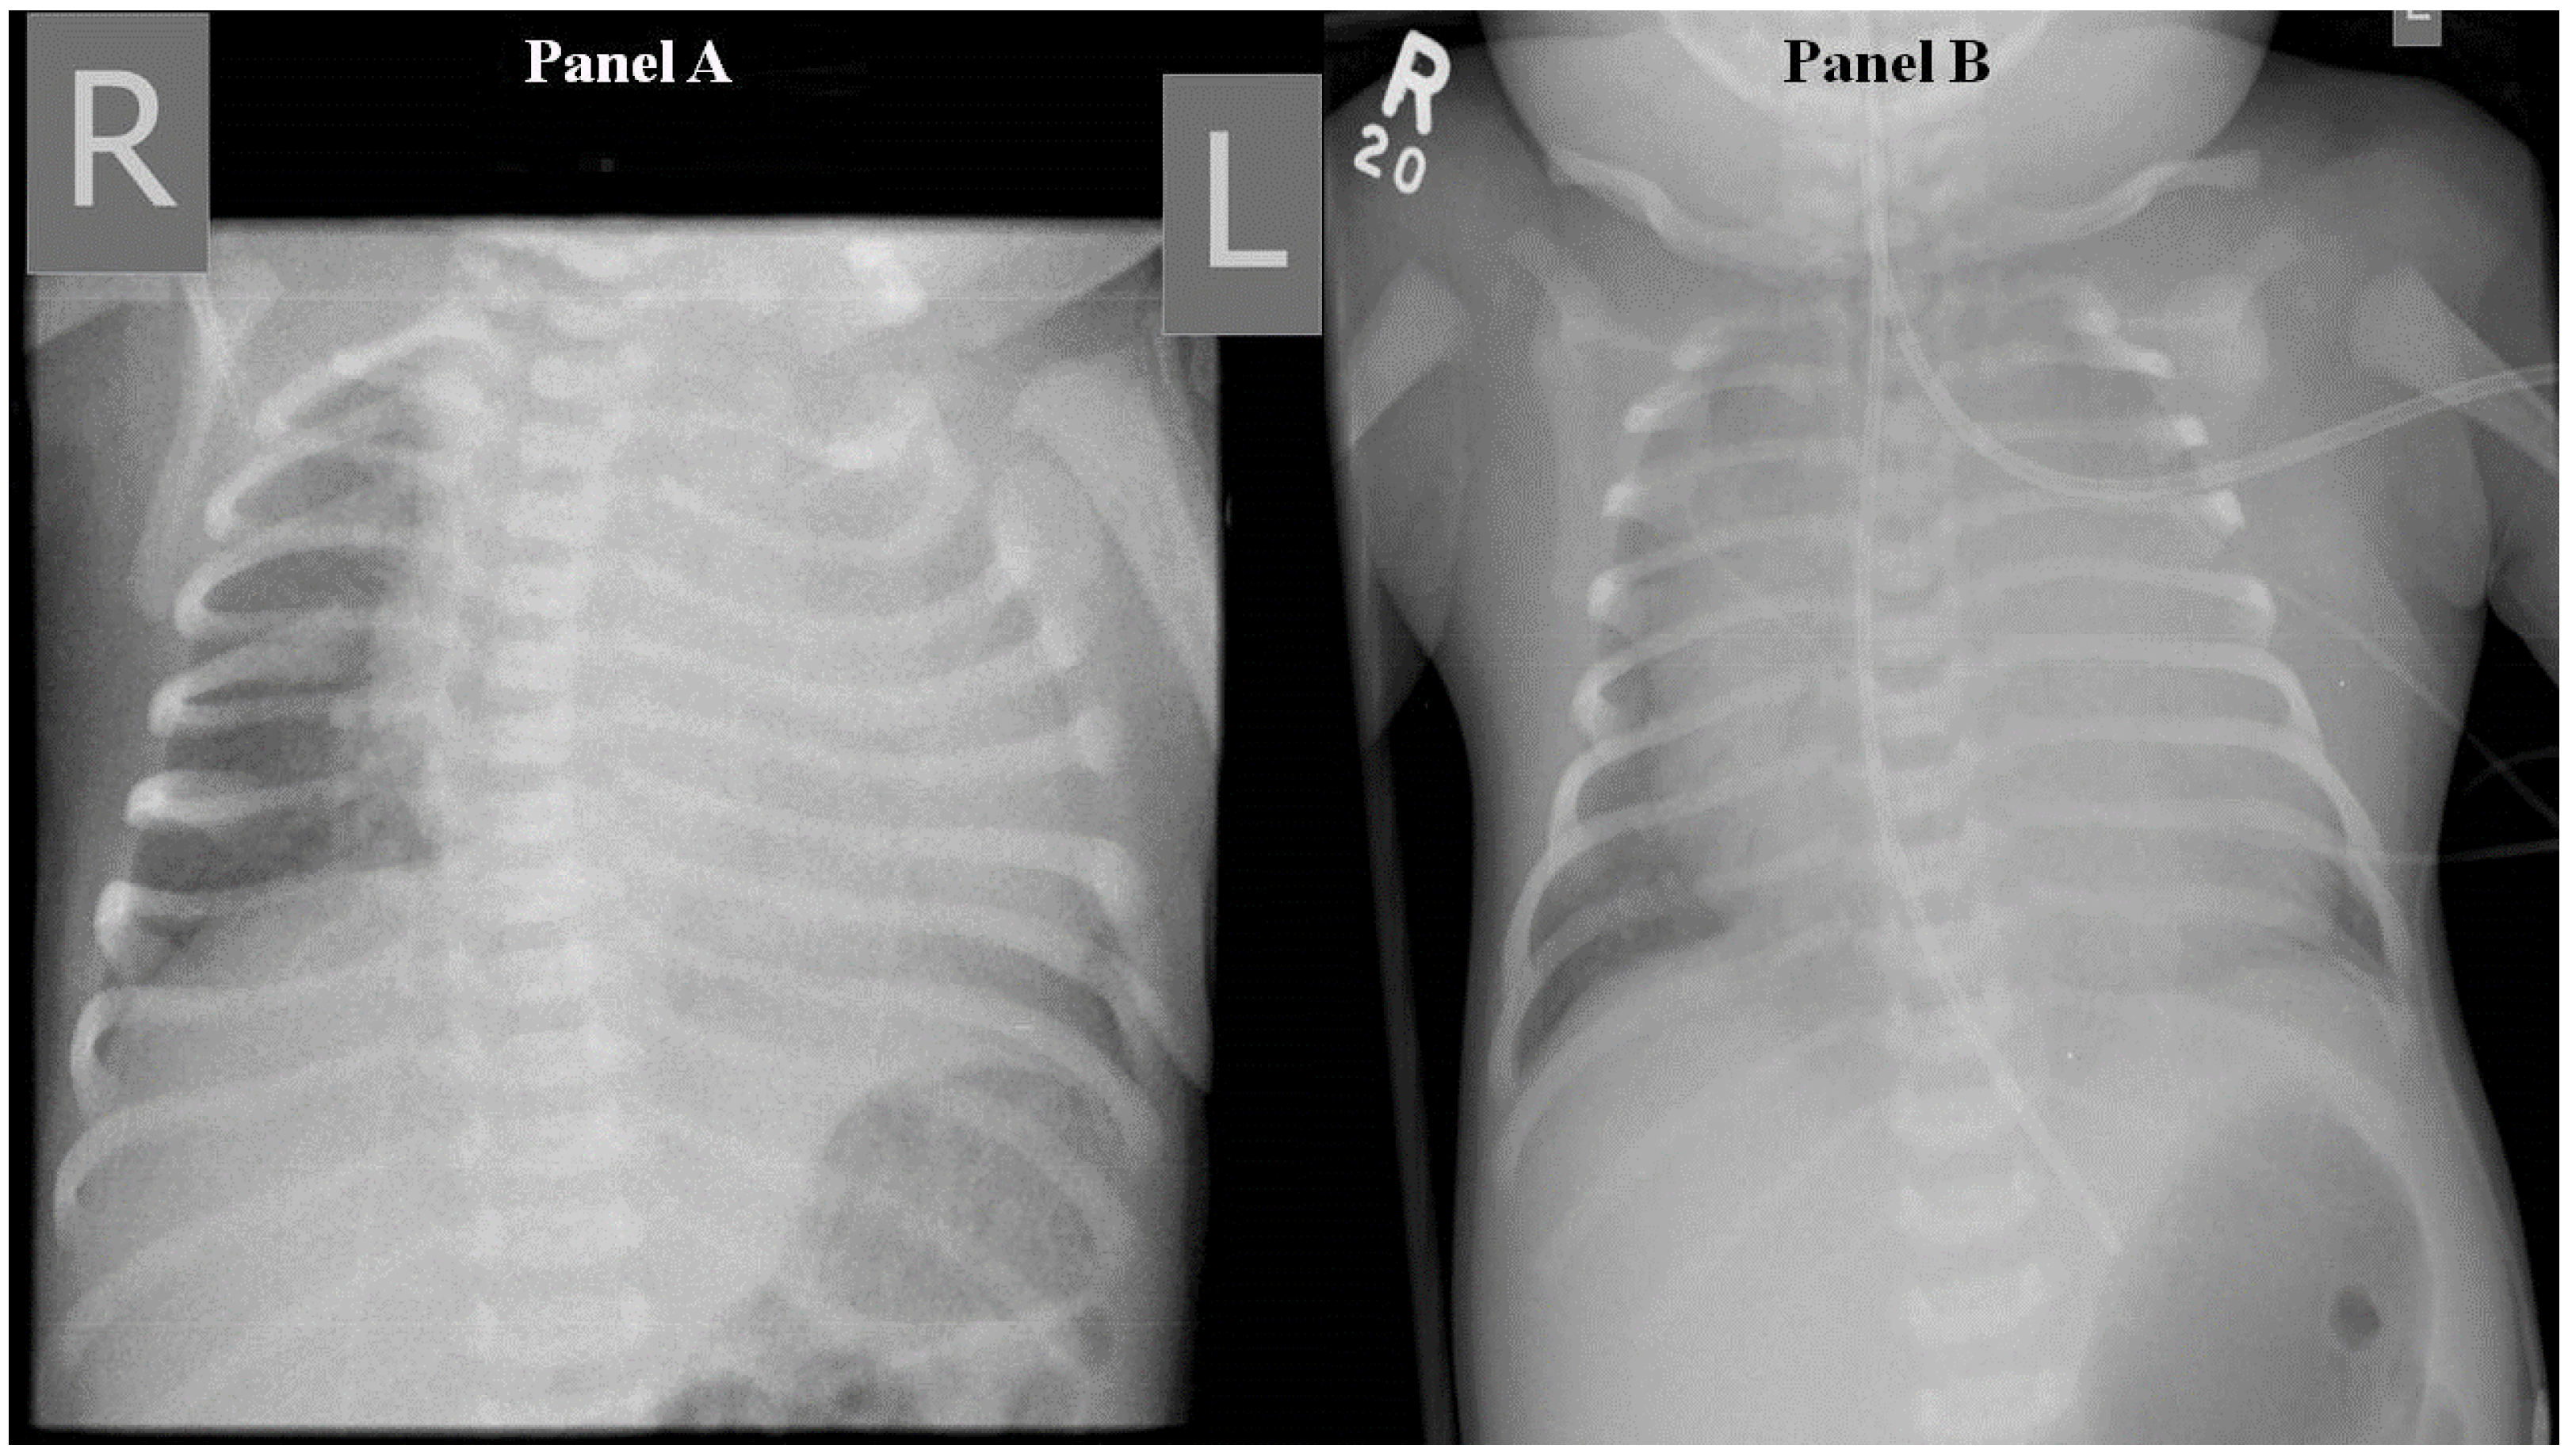

Full blood count, electrolytes, and inflammatory markers were normal on admission. Capillary blood gas showed metabolic acidosis (pH 7.24, pCO2 40, HCO3− 16.1 mmol/L, base excess −10.3, lactate 3.4 mmol/L). Chest X-ray showed cardiomegaly with no focal collapse or consolidation (Figure 1). The echocardiogram was normal, apart from a 2.9 mm patent ductus arteriosus with bidirectional flow and mild suprasystemic pulmonary hypertension.

Figure 1.

Frontal chest radiograph taken on day 1 demonstrating cardiomegaly predominantly in left chambers (Panel A) and worsening cardiomegaly on day 6 (Panel B). R denotes right side and L, left side.

On day 5 of life, the patient deteriorated with severe respiratory distress, poor perfusion, minimal responsiveness, oliguria, and hyponatraemia (Na 117 mmol/L). Examination revealed worsening generalized oedema, ascites, and hepatomegaly. This was attributed to congestive heart failure. Chest X-ray showed worsening cardiomegaly. The patient was managed with intubation and ventilation, fluid restriction, frusemide, bicarbonate correction, and the addition of cefotaxime.